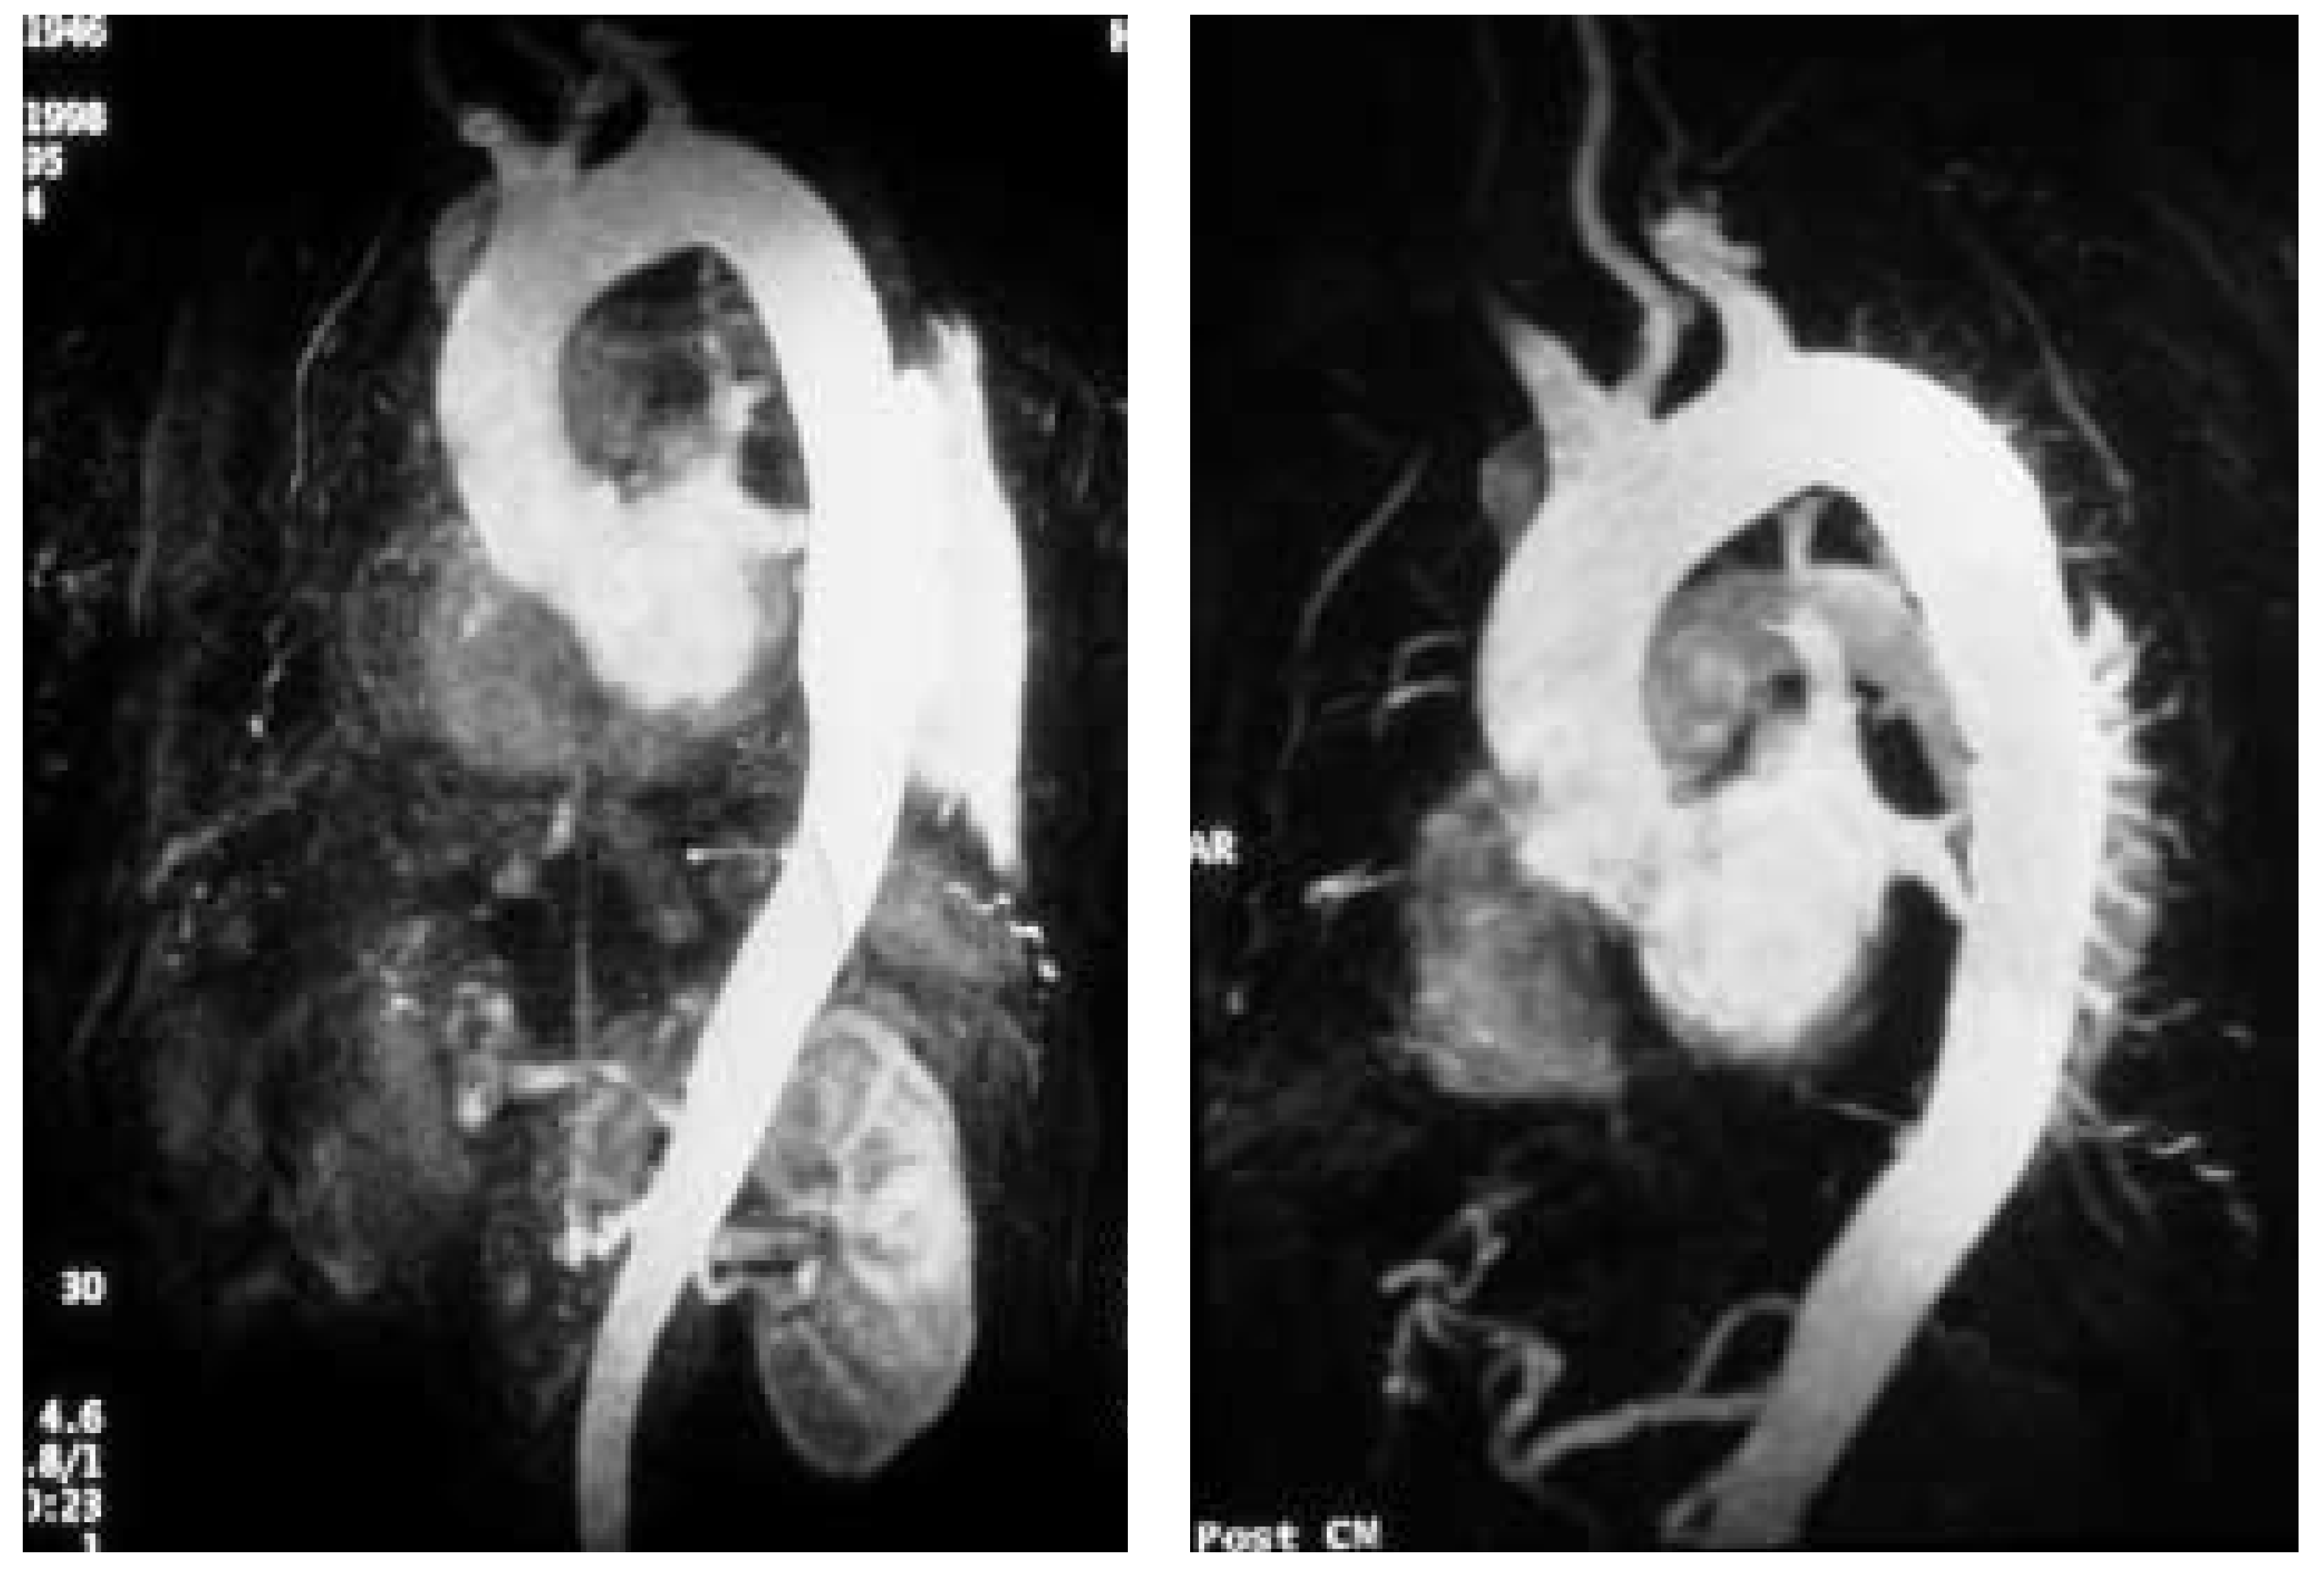

Figure 1. Magnetic resonance angiograms obtained before and after placement of a stent-graft. (A) Three-dimensional, maximum-intensity projection after injection of gadolinium-DTPA. There is a dual, open-lumen type B dissection; the entry to the perfused false lumen (black arrow) is located in the distal arch directly adjacent to the left subclavian artery. The white arrow indicates the false lumen. (B) Three months after successful placement of a TALENT™-stent-graft (Dacron-covered) directly onto the entry of the false lumen. The entry is completely sealed by the stentgraft and the false lumen in the thoracic and abdominal aorta is thrombosed (white arrow). The left subclavian artery is widely patent and the true lumen (black arrow) has widened as evidence of aortic remodeling.

The interventional management of Stanford type B (De Bakey type III) dissection and the use of stent-grafts evolved slowly in anticipation of the risk of paraplegia from spinal artery occlusion as seen in up to 18% after open surgery [11,12]. However, with further technical improvement a large series of cases has now been successfully treated by endovascular stent-graft placement covering entry tears in the descending aorta and even in the aortic arch. Recent studies have demonstrated that closure of proximal entry tears is essential to reconstruct the aortic wall and reduce total aortic diameter. Entry tear closure promotes depressurisation of false lumen, thrombus formation in the false lumen (Figure 2) and remodeling of the entire aorta [2,3,12]. In the near future combined surgical and interventional procedures even for proximal dissection are on the horizon [13,14,15].

Recent reports suggest that percutaneous stent-graft placement in the dissected aorta is safer and produces better results than surgery for type B dissection. Paraplegia may occur after use of multiple stent-grafts but still appears to be a rare phenomenon, especially when the stented segment does not exceed 16 cm. Results of short-term follow-up are excellent with a 1-year survival rate of >90%; tears can be readapted and aortic diameters generally decrease with complete thrombosis of the false lumen. This suggests that stent placement may facilitate healing of the dissection, sometimes of the entire aorta, including abdominal segments (Figure 1). However, late reperfusion of the false lumen has been observed occasionally underlining the need for stringent follow-up imaging. In some patients, follow-up imaging has revealed tears that had initially been overlooked, but required additional stents.